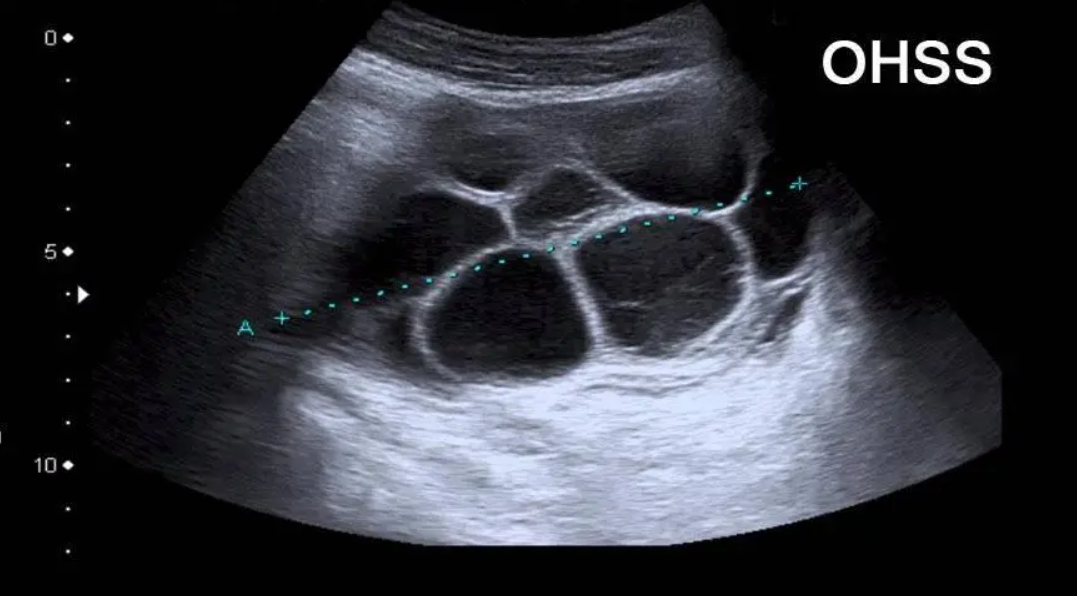

专家指出,在促排卵时,雌二醇是监测卵泡成熟和卵巢过度刺激综合征(OHSS)的重要指标。专家在促排期间精准用药,并全程通过验血和超声检查严密监测,掌握卵泡的发育进度和女性激素水平。当1~2个卵泡直径≥18mm或者2~3个卵泡直径≥17mm时注射破卵针,与36小时之后安排全麻无痛取卵,能够有效防止女性卵巢受到过度刺激。